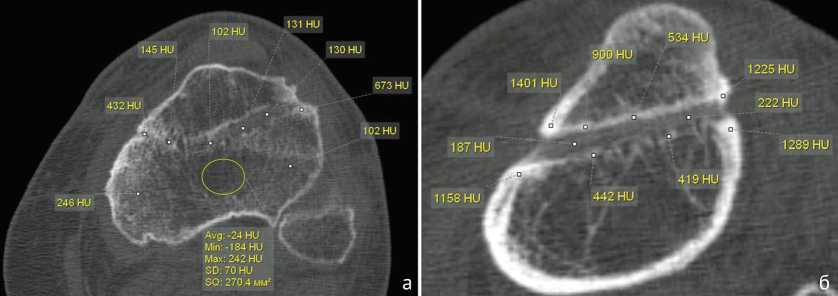

Спицевой канал был шире в области кортикальной пластинки. Плотность стенок спицевого канала увеличивалась до 480 [420;620] HU (медиана) (рис. 4, а). При локализации СО в дистальной трети большеберцовой кости и длительном течении заболевания (больше года) изменения в данной области проявлялись участками деструкции, нарушением структуры кости, появлением зон разрежения и склероза. Во всех случаях воспалительный и деструктивный процесс распространялся на кости стопы, сопровождаясь дефектами, изменением структуры с нарушением органотипического строения костей, зонами резорбции (рис. 4, б, в).

Рис. 4. МСКТ голеней пациентов со СО: а — пациентки 34 лет, MPR в сагиттальной плоскости; б — больного 56 лет, аксиальный срез, массивные периостальные наслоения, ассимилированные с корковой пластинкой; в — MPR этого же больного в сагиттальной плоскости

Увеличение ширины и нечеткие контуры спицевого канала наряду с увеличением плотности его стенок зарегистрированы на ранних стадиях СО. Ширину канала сравнивали с его размерами после удаления спицы у пациентов без воспалительного процесса (контрольная группа). Медиана ширины спицевого канала в области диафиза в этих случаях составляла 1,6 [1,4;1,7]. Ширина спицевого канала после удаления спицы при септическом остеомиелите в области диафиза колебалась в значительных пределах, — от 3,5 мм до 7,0 мм. Медиана ширины спицевого канала в диафизе у пациентов со СО составила 4,1 мм [межквартильный размах 3,8;5,1 мм]. Для сравнения, — в области эпифиза ширина спицевого канала была меньше и составляла 2,6 мм [2,8;3,1 мм], что связано с анатомическими особенностями строения проксимального отдела большеберцовой кости в этой зоне (рис. 5).

Рис. 5. МСКТ голени пациентов 36 лет (а) и 42 лет (б) со СО. Ширина спицевого канала: а — аксиальный срез; б — MPR в сагиттальной плоскости